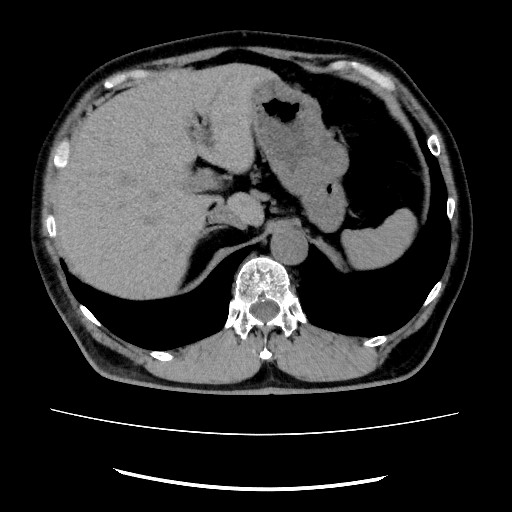

直腸肛門疾患に特化したCT撮影法

当院では、肛門・直腸疾患に特化した独自のCT撮影法を行っています。

従来の腹部CTが仰向けで撮影するのに対し、この方法ではうつぶせで撮影し、さらに直腸の形や走行に合わせて断面角度を調整することで、肛門周囲の病変をより鮮明に映し出すことが可能です。

また、3D画像によって痔瘻の走行を立体的に描出することもできます。

一般的撮影法

肛門病変に特化した撮影法